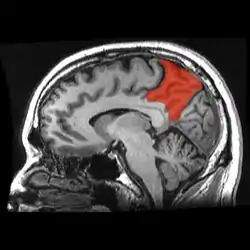

![]() Sagittal MRI slice with the precuneus shown in red. | |

In neuroanatomy, the precuneus is the portion of the superior parietal lobule on the medial surface of each brain hemisphere. It is located in front of the cuneus (the upper portion of the occipital lobe). The precuneus is bounded in front by the marginal branch of the cingulate sulcus, at the rear by the parieto-occipital sulcus, and underneath by the subparietal sulcus. It is involved with episodic memory, visuospatial processing, reflections upon self, and aspects of consciousness.